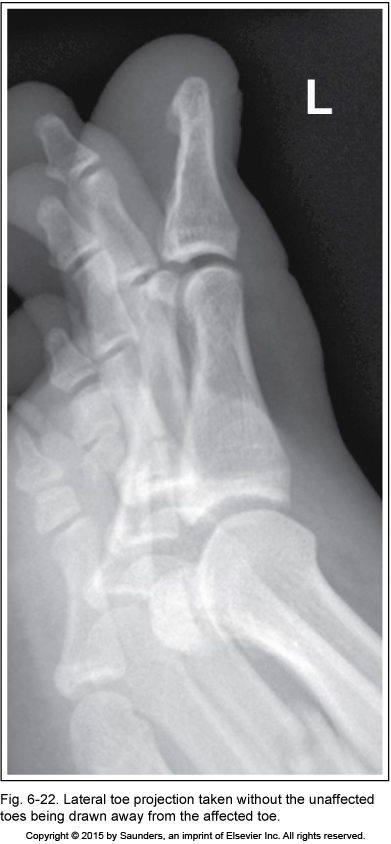

lateral toe

inadequate obliquity

unaffected toes are not pulled away